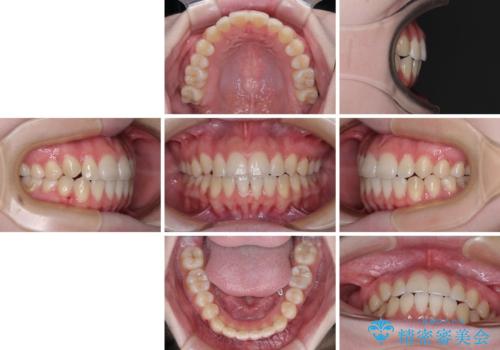

カリエール・ディスタライザーとインビザラインを用いた八重歯の改善

カリエールディスタライザーを併用したことで、左側臼歯の咬み合わせを確実に改善させることができました。